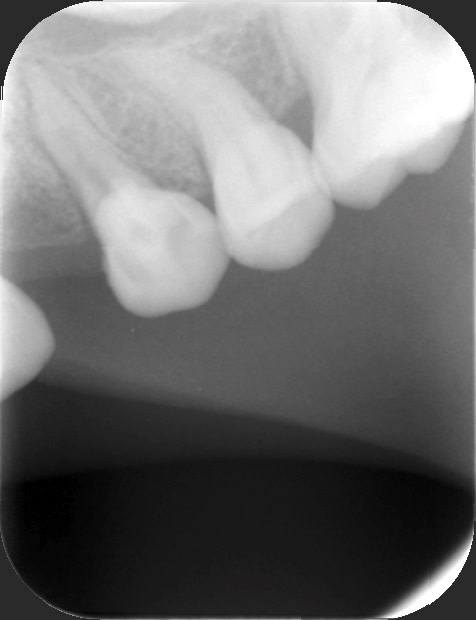

qu’est ce que vous conseillerez à maman de faire pour cette 14 qui est douloureuse à la percussion ?

846e6358 30e4 4631 ac1b 1498f94aeade lwcuv0 - Eugenol

4a338550 6a5b 47ea b2a7 d3cb675c5076 oni5gh - Eugenol

Ylfwcw979cz1jnx9gfqeaxndiuzk - Eugenol

Algi

03/06/2021 à 14h37

Elle est vivante ta dent ?

La radio est bof bof mais il semble y avoir un élargissement desmodontal...

Nécrosée ? Souffrance oclusale?

Et la 13 elle est où ?